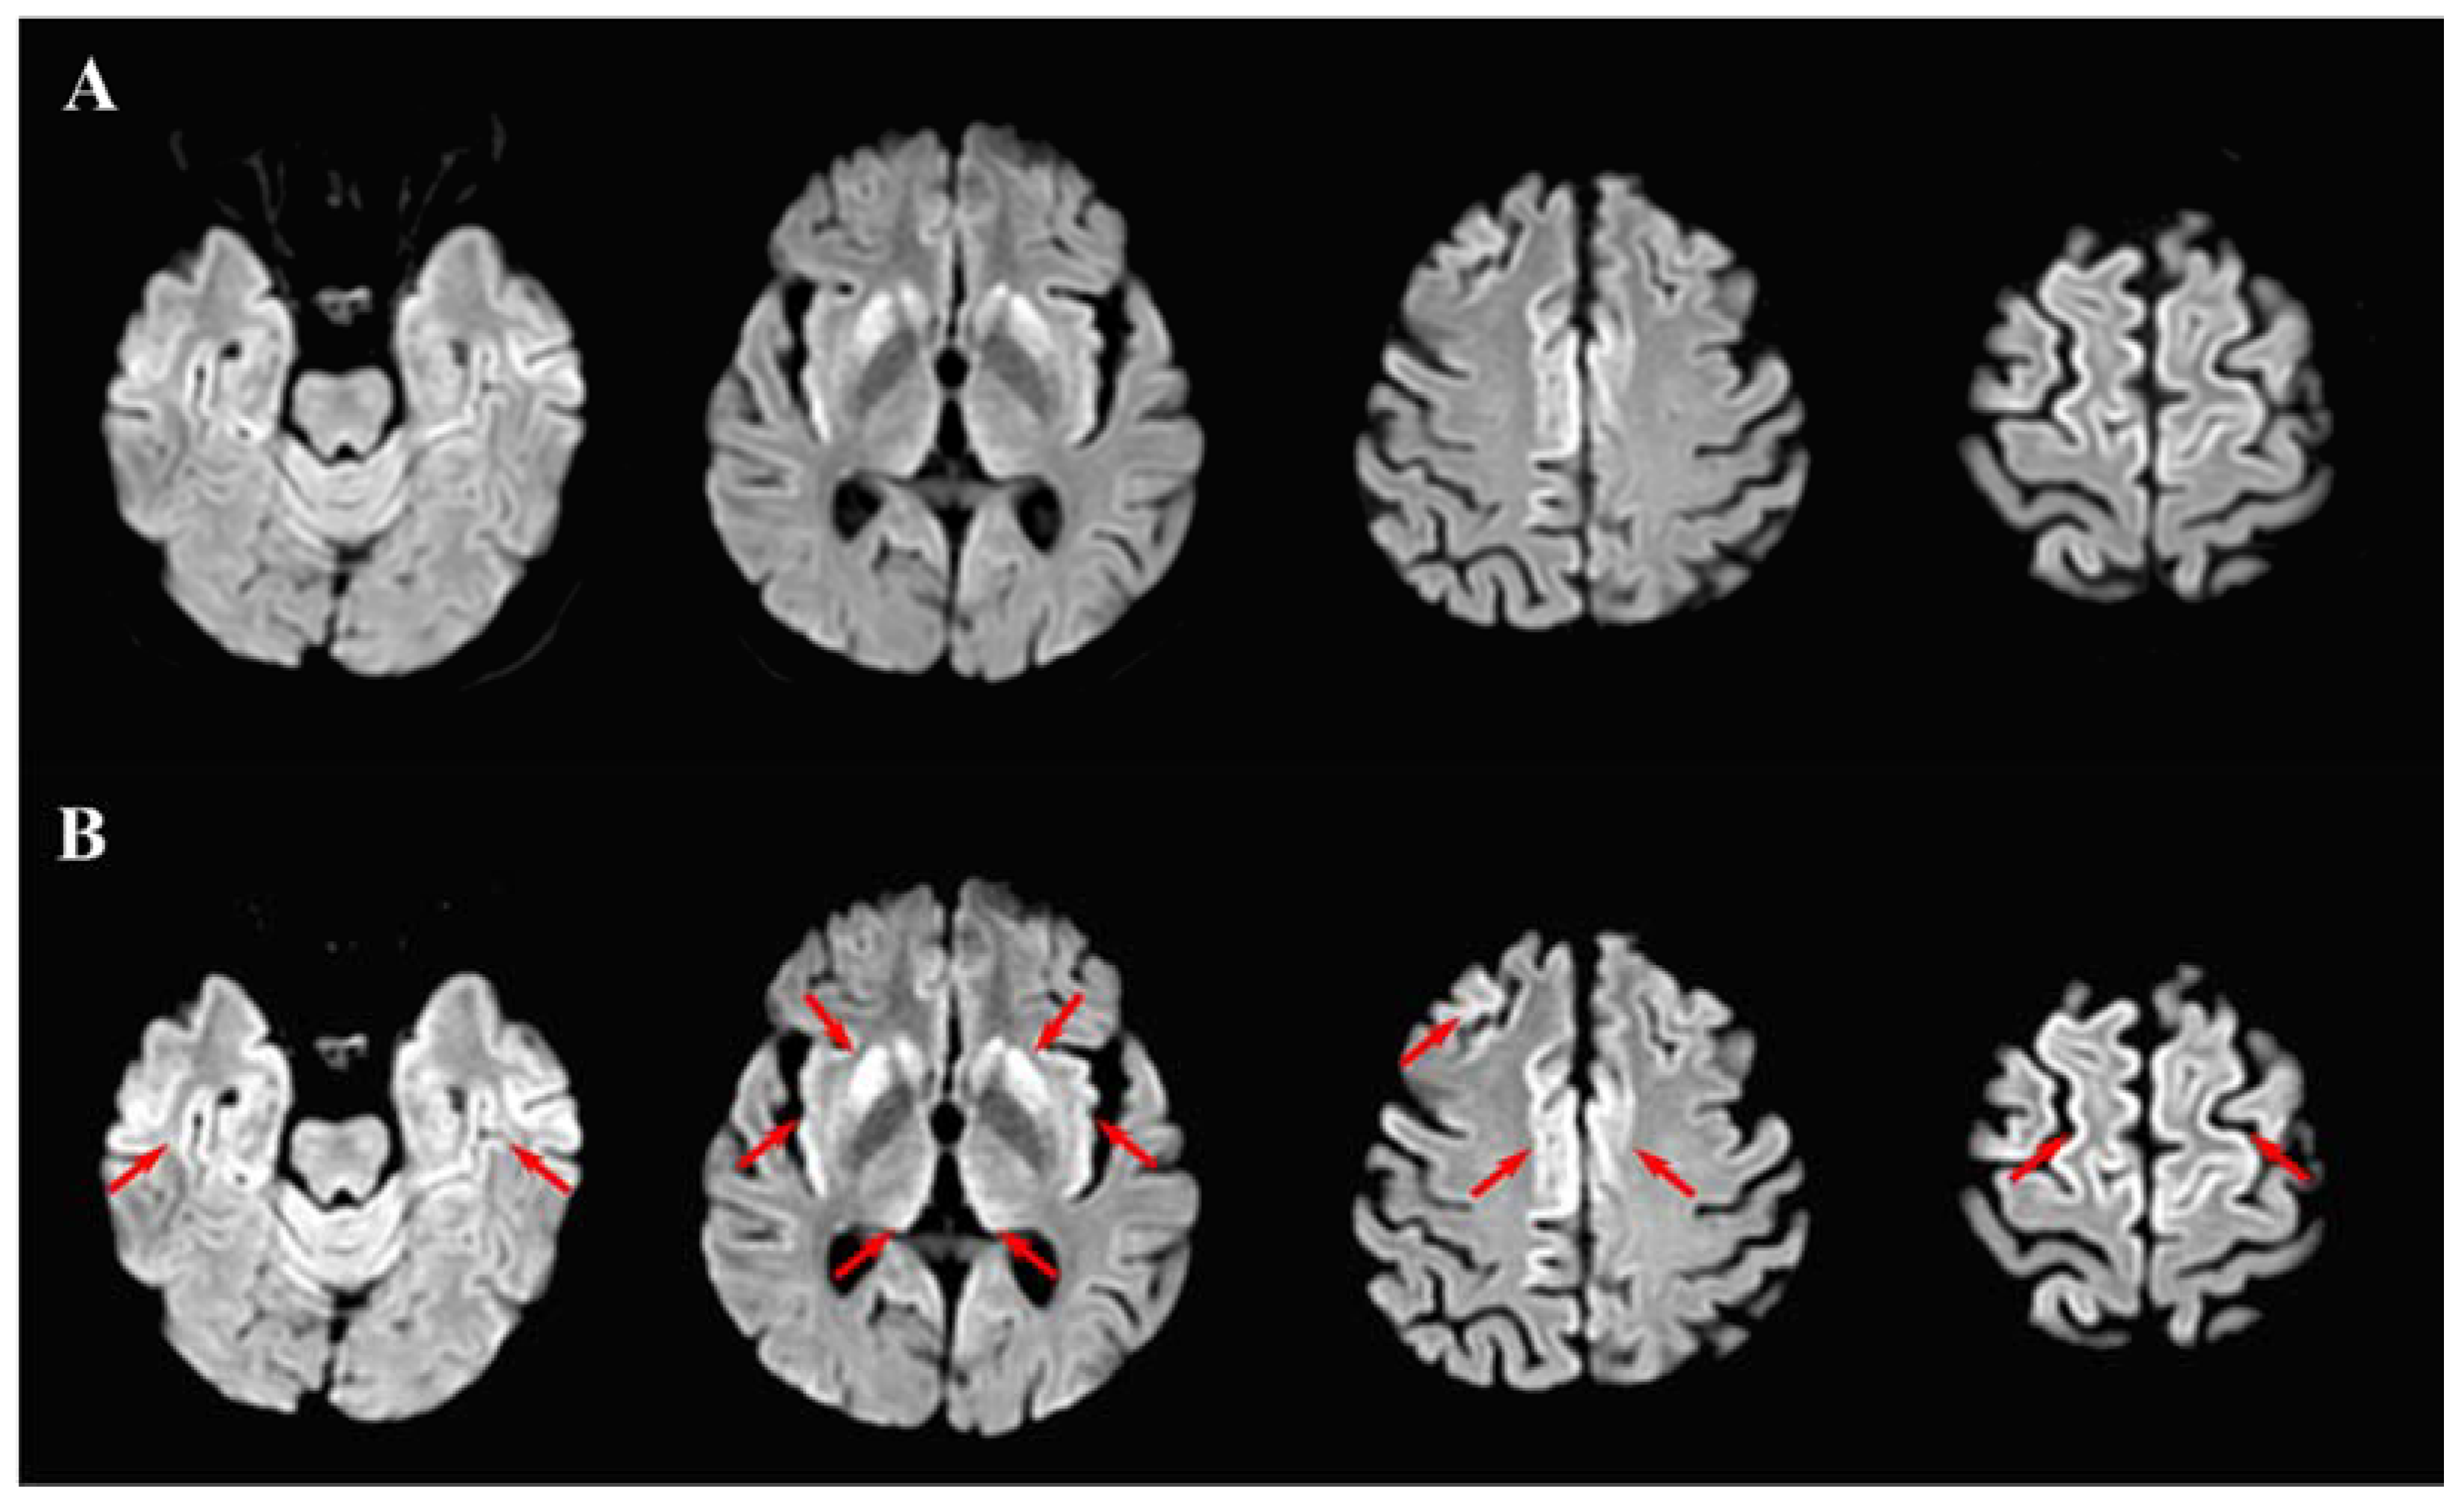

2. Case Report